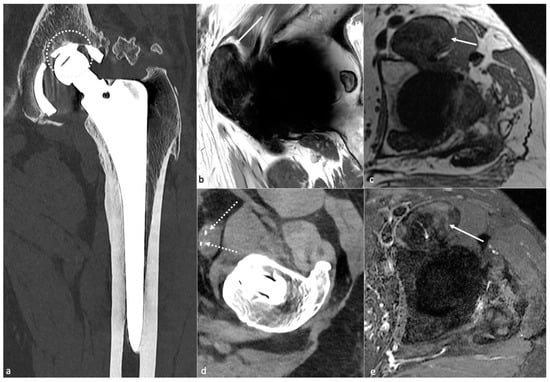

3.4.3. MRI

- Bone marrow edema was frequent all over the femoral stem and in the central acetabular zone at 3 and 6 months after surgery, decreased during follow-up, and sometimes persisted in Gruen zones 1 and 7 overtime, but often in only one area;

- Inferomedial edema in the acetabulum was infrequent and should raise suspicion for pathology;

- Periprosthetic bone resorption was frequent during the second post-operative year in Gruen zones 1 and 8 but never thicker than 2 mm;

- Periosteal edema was shared on the femoral side with a decrease over time, rarely present at two years, and only in non-adjacent Gruen zones, without acetabular side attempt;

- In the first six months, soft-tissue edema was a constant feature in the surgical access route but never occurred in the second year;

- Joint effusion was decreasing over time but could be present in the lateral aspect of the joint capsule at two years [19].